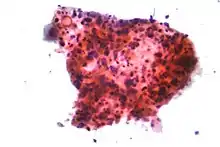

Lung cancers are classified according to histological type.[12] This classification is important for determining both the management and predicting outcomes of the disease. Lung cancers are carcinomas – malignancies that arise from epithelial cells. Lung carcinomas are categorized by the size and appearance of the malignant cells seen by a histopathologist under a microscope. For therapeutic purposes, two broad classes are distinguished: non-small-cell lung carcinoma and small-cell lung carcinoma.[69]

In SCLC, the cells contain dense neurosecretory granules (vesicles containing neuroendocrine hormones), which give this tumor an endocrine or paraneoplastic syndrome association.[74] Most cases arise in the larger airways (primary and secondary bronchi).[13] Sixty to seventy percent have extensive disease (which cannot be targeted within a single radiation therapy field) at presentation.[2]